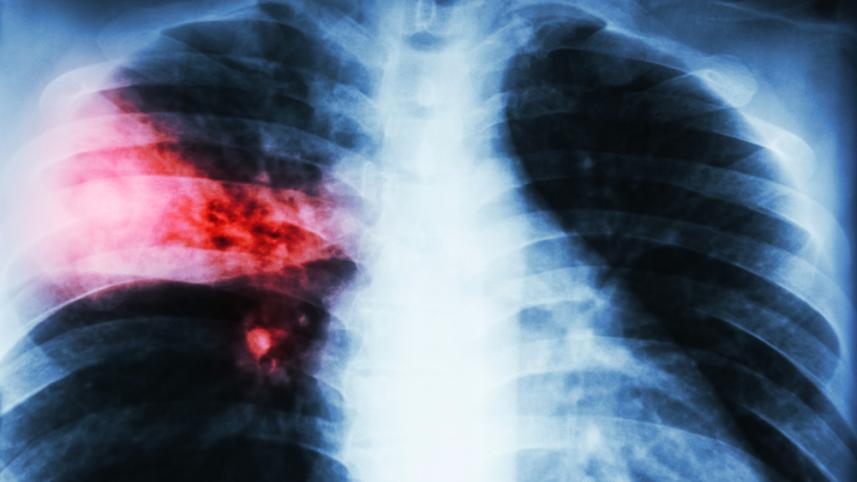

অধ্যাপক সোহেল মাহমুদ বলেন, জ্বর, কাশি, বুকে ব্যথা এবং কফ হলুদ হয়ে যাচ্ছে এমন লক্ষণ দেখা দিলে অবশ্যই চিকিৎসকের পরামর্শ নিতে হবে। সাধারণত রক্ত পরীক্ষা ও বুকের এক্স-রে করাই যথেষ্ট নিউমোনিয়া রোগ নির্ণয়ের জন্য। নিউমোনিয়া দ্রুত নির্ণয় করে চিকিৎসা শুরু করা গেলে সিভিয়ার হওয়ার আশঙ্কাও কমে যাবে।